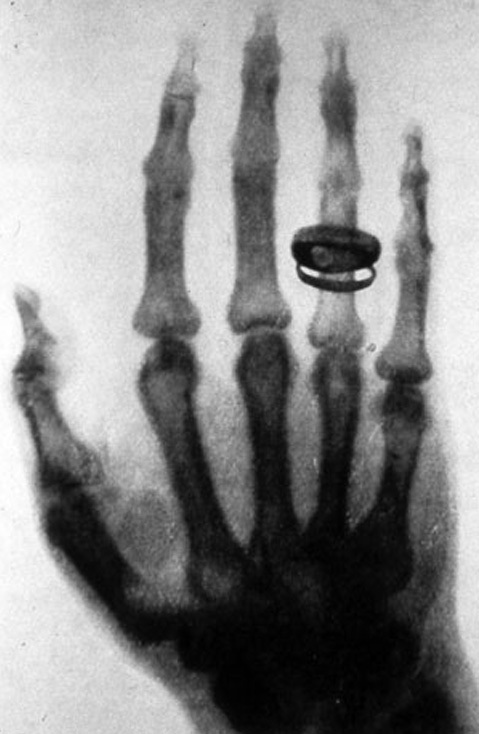

“Vision,” he says, “is extremely powerful. It is a primary source of sensory information in human beings, and it is so much a part of how most people understand the world around them that, while we might say that, ‘Seeing is believing,’ the converse is also true. Especially in medicine. Not seeing is often not believing. Humans are inclined to be skeptical if we cannot see something. So when Wilhelm Röntgen took the first X-ray picture of his wife’s hand in 1895, he changed everything. Suddenly clinicians could see inside a living body, which throughout human history up until that point, was impossible without some kind of surgery. It was one of those moments after which the world was changed in an important and permanent way. Suddenly, what had been invisible was revealed, and there was just no going back.”

But, remarkably, given the profound impact of X-rays on the way medicine was practiced, it was nearly 80 years before the field of medical imaging advanced past that original breakthrough.

“Up until 1974,” says Dr. Bryan, “which was when I was training as a neuroradiologist, X-rays remained the only imaging modality clinicians had available to them. That’s right. It was just X-rays, all the way up to 1974. The technology was refined over time of course, and clinicians did very creative things with the technology they had, but all a doctor could see was bone. There were no images of soft tissue. No images of the brain, or the heart, no comparative studies of the impact chemotherapy was having on a tumor, or functional images to help determine the health of an organ. Surgeons, before 1974, practiced in a very different world than they do now.”